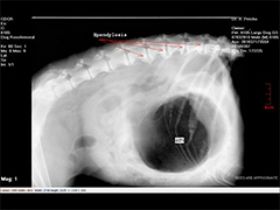

הסתיידות חוליות הגב אצל כלב- ספונדילוזיס